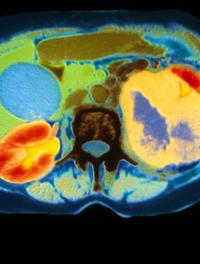

La polykystose rénale autosomique dominante (PRAD) est la quatrième cause d’insuffisance rénale chronique terminale chez l’adulte. [...]

La polykystose rénale autosomique dominante est à l’origine de 8 à 10 % des greffes de rein. L’augmentation progressive du volume des [...]